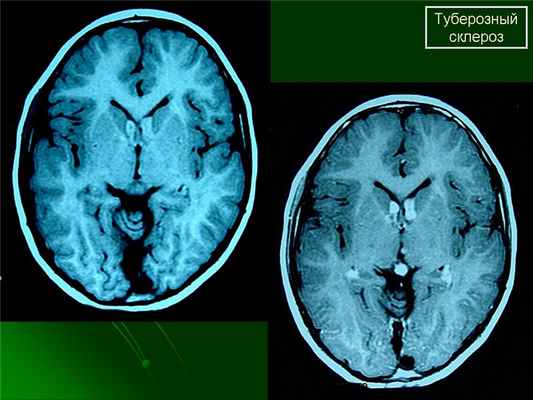

Наиболее типичными нарушениями в головном мозге являются корковые туберсы и субэпендимарные узлы. Туберсы могут быть как единичными, так и множественными, располагаются в виде выступов над единичной или прилегающими бороздами коры, расширяя их. Субэпендимарные узлы локализуются в стенках боковых желудочков и, реже, в стенках III и IV желудочков мозга. У новорожденных субэпендимарные узлы редко бывают кальцифицированными. По мере роста ребенка наблюдается постепенное отложение кальция в субэпендимарных узлах.

Субэпендимарные узлы в 10% случаев трансформируются в гиганто-клеточную астроцитому, которые манифестируют обычно между 5 и 10 годами жизни, имеют тенденцию к росту и локализуются у отверстия Монро

Субэпендимарные кальцификаты и корковые туберсы на КТ головного мозга ребенка с туберозным склерозом

Субэпиндемальные узлы и корковые туберсы на МРТ

МРТ головного мозга при туберозном склерозе. Участки изменения МР-сигнала неправильной формы в коре и подкорковом белом веществе — так называемые корковые туберсы.

КТ головного мозга при туберозном склерозе. Видны кальцинированные субэпендимальные узелки в стенках боковых желудочков.